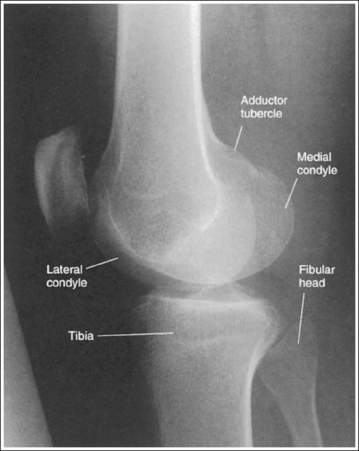

The knee demonstrates an AP projection. The medial and lateral femoral epicondyles are in profile, the femoral condyles are symmetrical, the intercondylar eminence is centered within the intercondylar fossa, and the tibia is superimposed over 0.25 inch (0.6 cm) of the fibular head.

• To obtain an AP knee projection, place the patient in a supine position with the knee fully extended. Internally rotate the leg until an imaginary line drawn between the medial and lateral femoral epicondyles is positioned parallel with the IR (Figure 6-71). This positioning places the medial and lateral femoral epicondyles at equal distances from the IR as well as medially and laterally in profile, respectively. It also centers the intercondylar eminence within the intercondylar fossa and draws the fibular neck and a portion of the fibular head from beneath the tibia.

• Effect of rotation. If the femoral epicondyles are not positioned parallel with the IR, an AP projection has not been obtained. If the patient's leg was not internally rotated enough to place the epicondyles at equal distances from the IR, they are not in profile, the medial femoral condyle appears larger than the lateral condyle, and the tibia is superimposed over more than 0.25 inch (0.6 cm) of the fibular head (see Image 54). If the patient's leg was internally rotated more than needed to place the femoral epicondyles at equal distances from the IR, the epicondyles are not demonstrated in profile, the lateral femoral condyle appears larger than the medial condyle, and the tibia is superimposed over less than 0.25 inch (0.6 cm) of the fibular head (see Image 55).